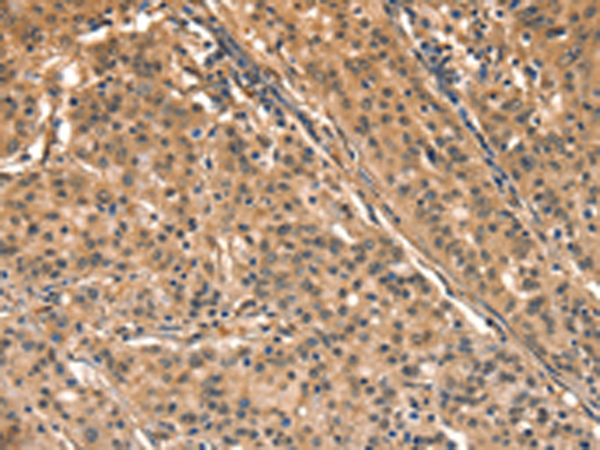

分类: 科研抗体货号: P04896别名: HGAL; GCAT2; GCET2应用: IHC反应种属: Human